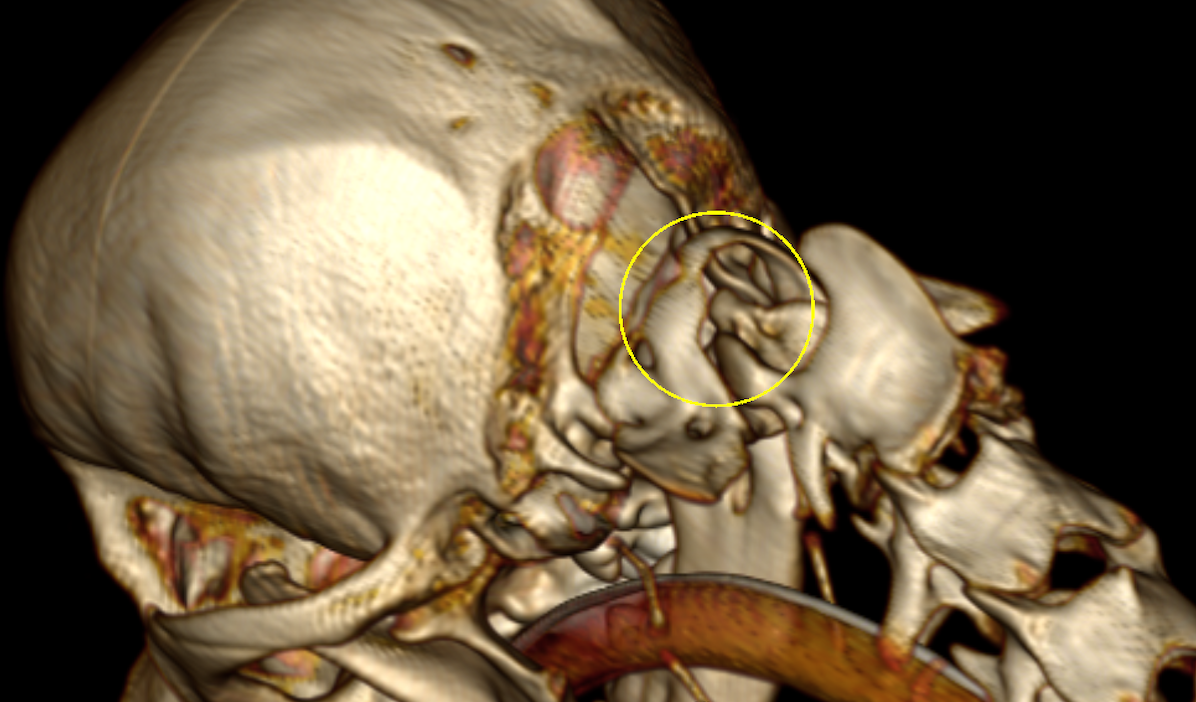

左がCT画像、右がMR画像です。2番めの頚椎である軸椎の歯突起が神経を圧迫してしまっているのがわかります。

CTを3Dにしたものです。立体的に骨の形状(歯突起が不安定になっている)がわかります。また、後頭骨の一部が欠損しています。